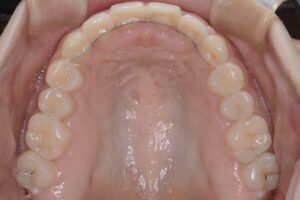

矯正治療終了(上顎)